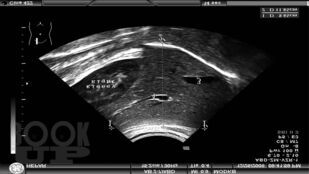

В справочно-практическом руководстве приведены и систематизированы планиметрические (размерные) и количественные показатели внутренних органов при ультразвуковых исследованиях у детей и взрослых. Даны количественные показатели внутрисосудистой гемодинамики артерий различных бассейнов в норме. Представлены количественные и гемодинамические показатели при ультразвуковом исследовании сердца как у детей, так и у взрослых. Эти данные помогут отличить норму от патологии. Приведена оценка степени выраженности клапанных пороков сердца. Изложены методологические основы проведения измерений при ультразвуковых исследованиях.

В новое издание включены главы, где предлагаются объективные ультразвуковые критерии при экстренной абдоминальной патологии (острый аппендицит, кишечная инвагинация, гипертрофический пилоростеноз), УЗИ тазобедренных суставов у детей до года. Приведены таблицы для определения срока беременности в первом, втором и третьем триместрах.